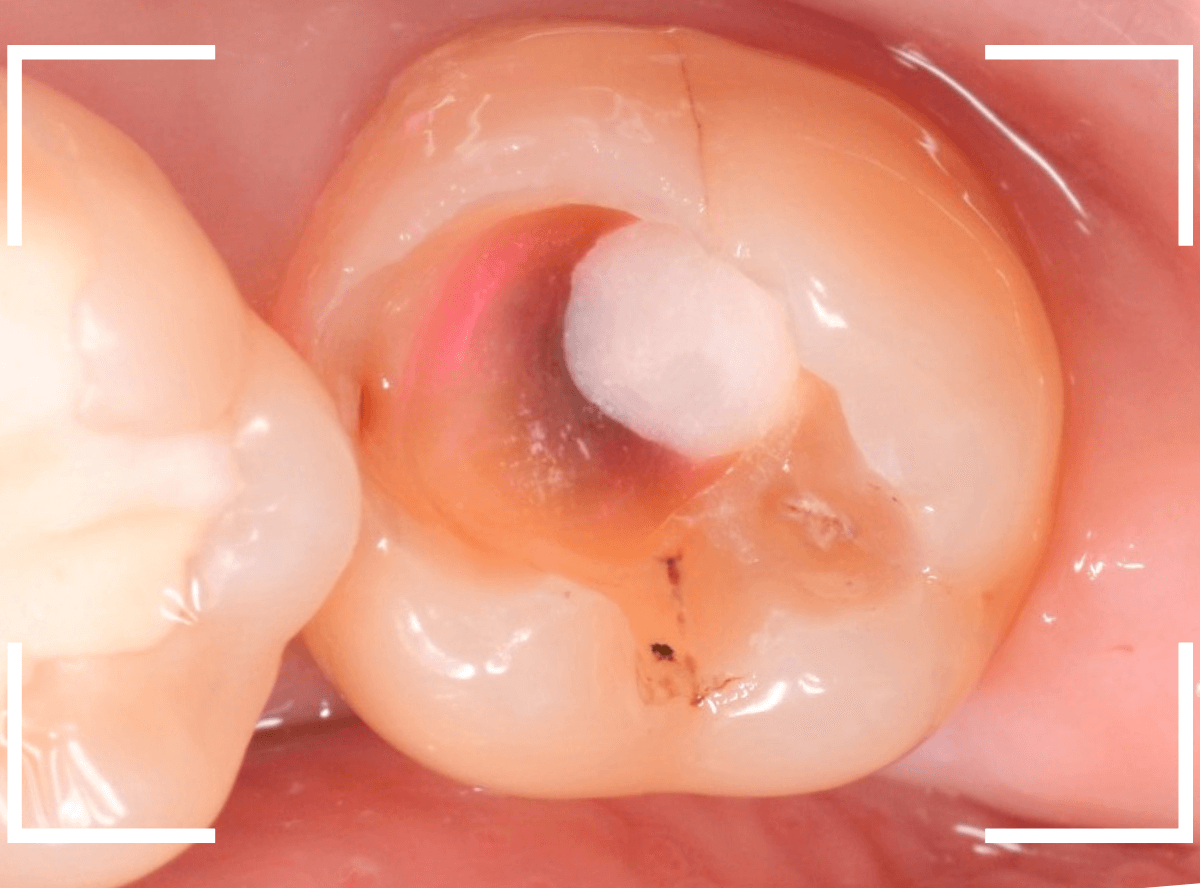

Case.15 歯の側面のレジンの中のわかりづらい虫歯

検診で、金属のつめ物のの中と、歯の側面に虫歯が見つかった方です。

まずは、手前(左)側の治療です。

こちらが、お口の中を見たところです。

〇部の中に虫歯があると思われます。

今回のように、金属のつめ物やレジン治療をしてある歯の側面の虫歯の診断はわかりづらく、難しいです。

金属のつめ物を外したところです。

この白いセメントの中に虫歯があると思われます。

セメントを除去したところです。

赤く染まっている部分が虫歯です。

真っ赤ですね(^^;)

まだ薄く染まっています。

もう少し除去する必要があります。

全ての虫歯が取れました、かなり深い神経まで近い虫歯でした。

金属のつめものをを外します。

つめものの下で虫歯になっていたせいで、虫歯と一緒に手前側のエナメル質がガリっと欠けてきました(><)

前の治療でつめたセメントを外しつつ、虫歯治療を行います。

写真ではわかりづらいですが、赤く染まった部分を中心に、虫歯がかなり広がっています。

虫歯を全て取り切ったところです。

神経スレスレの部分まで広がった虫歯で、最後は神経に触らないようにエキスカを使った、手探りでの虫歯治療になりました。